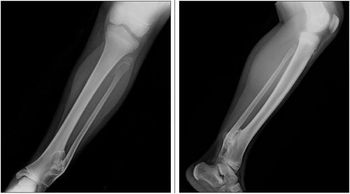

An apparently healthy 9-year-old girl noted to have left ankle mass during well-child checkup. Her last well-child visit was 3 years earlier. Medical history unremarkable. She denied fevers, weight loss, night sweats, and chills. No family history of bone deformities or growth disturbances.